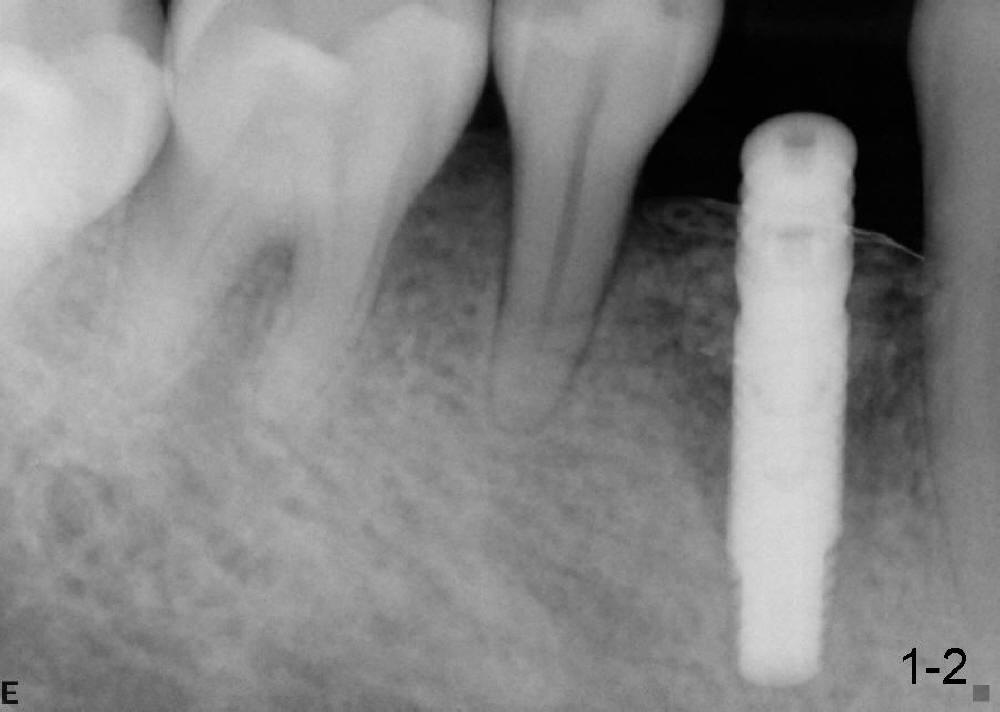

沐旭升医师送来两例植骨病例:第一例使用金属网(图一);第二例上颌骨头高度3.4 mm (CT 显示),上颌窦提高术植骨(侧面进路),同期植牙(图二)。打开每张图看评论。

Case1 is bone graft with metal mesh. Case 2 is bone graft with sinus lift through window, since the  existing bone only has 3.4 mm in the CT film (英文部分由沐医生提供).